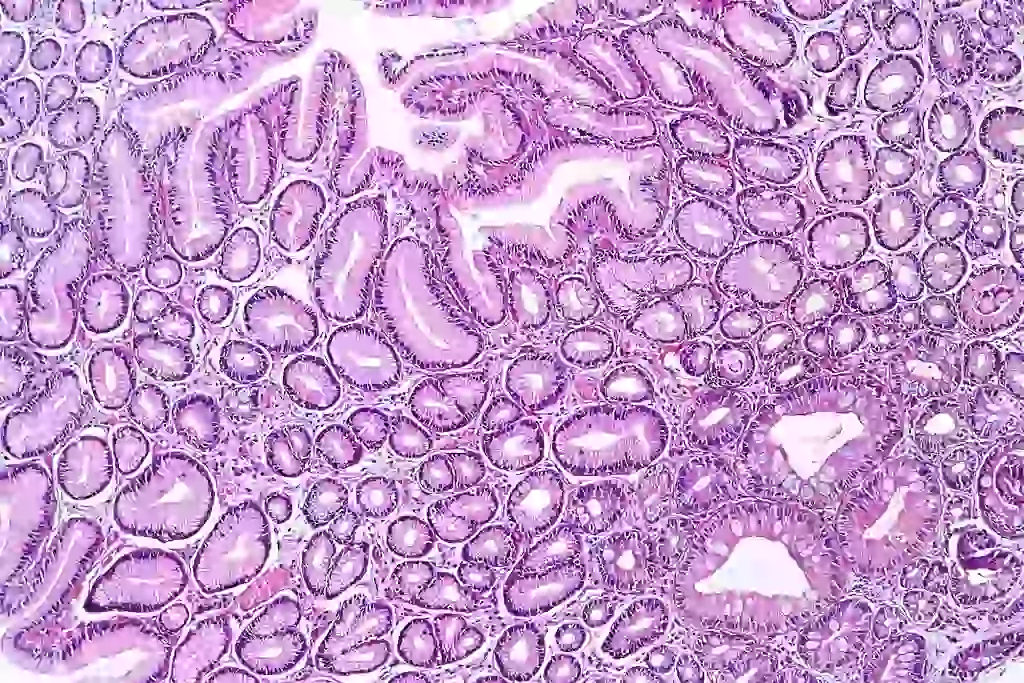

La metaplasia, chiamata anche cistite trigonale, trigonite pseudomembranosa, trigonite granulare, o uretrotrigonite, è un insieme di placche bianco-grigiastre in rilievo (tipo gli Appennini su un plastico geografico tridimensionale). Queste placche interessano prevalentemente il trigono vescicale (la parte posteriore ed inferiore della vescica).

La normale e non patologica metaplasia, in risposta ai continui stimoli irritanti infettivi, estrogenici, infiammatori e meccanici, può però trasformarsi in un tessuto cheratinizzato, cioè duro, ispessito e senza elasticità: la leucoplachia.

Il trigono, l'uretra e la vagina hanno la stessa origine embrionale, pertanto i tessuti di queste tre strutture saranno molto simili. Essendo molto simile al tessuto squamoso vaginale, il tessuto del trigono sarà molto suscettibile alla variazione degli estrogeni durante il ciclo mestruale e diventa più spesso e più evidente a causa di vari stimoli irritativi cronici: ormonali, chimici, infettivi, meccanici. È stato evidenziato infatti che la somministrazione di estrogeni causa l'ispessimento del trigono e l'estensione delle placche. La metaplasia, infatti, insorge in donne fertili (quando la quantità di estrogeni è massima, è assente prima dell'adolescenza, è rarissima negli uomini, diminuisce o scompare con la menopausa, varia durante le fasi del ciclo mestruale, parallelamente a ciò che avviene nel tessuto vaginale.

La normale e non patologica metaplasia, in risposta ai continui stimoli irritanti infettivi, estrogenici, infiammatori e meccanici, può però trasformarsi in un tessuto cheratinizzato, cioè duro, ispessito e senza elasticità: la leucoplachia. La leucoplachia viene frequentemente riscontrata infatti in pazienti con cistite cronica, cistite interstiziale, calcolosi vescicale, in portatori di catetere vescicale a permanenza ed in pazienti con carenza di vitamina D.

Il termine leucoplachia o leucoplasia significa “placche bianche”. Il nuovo tessuto formato infatti ha un aspetto bianco, in rilievo, ispessito. Al di sotto di questo strato di leucoplachia la mucosa è erosa, talvolta emorragica ed imperniata di sostanze infiammatorie, che possono raggiungere anche lo strato muscolare sottostante alterando anche a questo livello le cellule che lo compongono. Anche il tessuto tra una placca e l'altra risulta irritato e sofferente. L'ispessimento della parete vescicale può raggiungere anche i 3 cm.

La leucoplachia del trigono è un reperto comunissimo tra le donne sottoposte a cistoscopia e biopsia. Se non subentra un'eccessiva cheratinizzazione, la leucoplachia regredisce con il regredire dell'infiammazione. Più è avanzato il processo di cheratinizzazione e più la leucoplachia diventa irreversibile. La leucoplachia è considerata una lesione precancerosa perché presenta, rispetto a una metaplasia normale, una potenzialità maggiore di trasformazione in carcinoma a cellule squamose. È doveroso sottolineare però che la frequenza di tumore vescicale nella donna è di circa una su 100.000 e che fra queste pochissime donne solo il 2% ha un carcinoma a cellule squamose, cioè che origina da tessuti leucoplasici. Il restante 98% dei tumori vescicali deriva da tessuti senza leucoplasia (cioè da tessuto transizionale “normalissimo”). Considerando quindi la ridotta frequenza di tumore vescicale squamoso e l'elevata casistica diagnostica di leucoplasia nelle donne sottoposte a cistoscopia, risulta infondato l'eccessivo allarmismo che viene fatto sulla concerogenicità di questa alterazione vescicale.